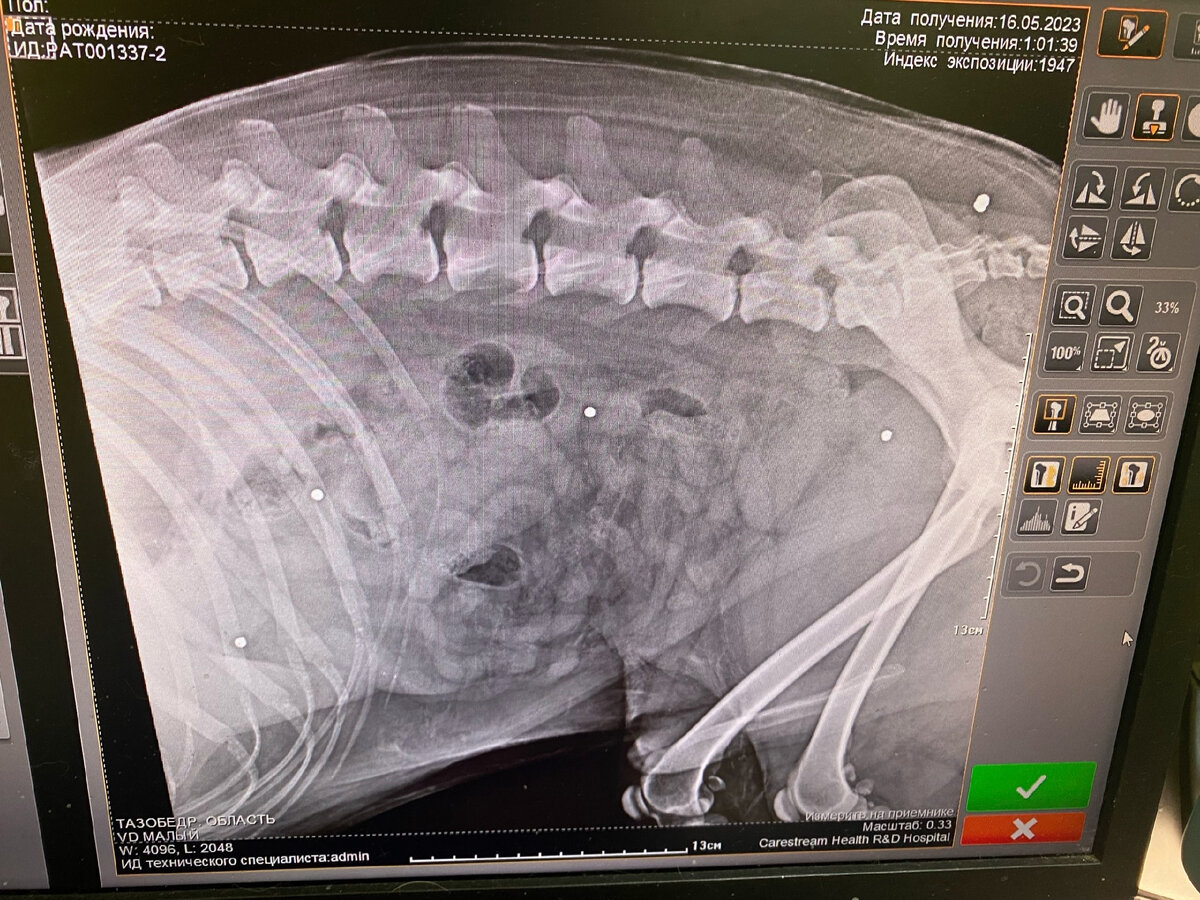

По итогам этой ночи стало понятно, что ничего непонятно. Анализы у него и правда, хоть в космос запускай. Рентген ничего феноменального не показал. Да, старая дробь по всему телу. Но не более. А он воет, а ему адски больно, живот болит. И сознание теряет.

Дробь по всему телу